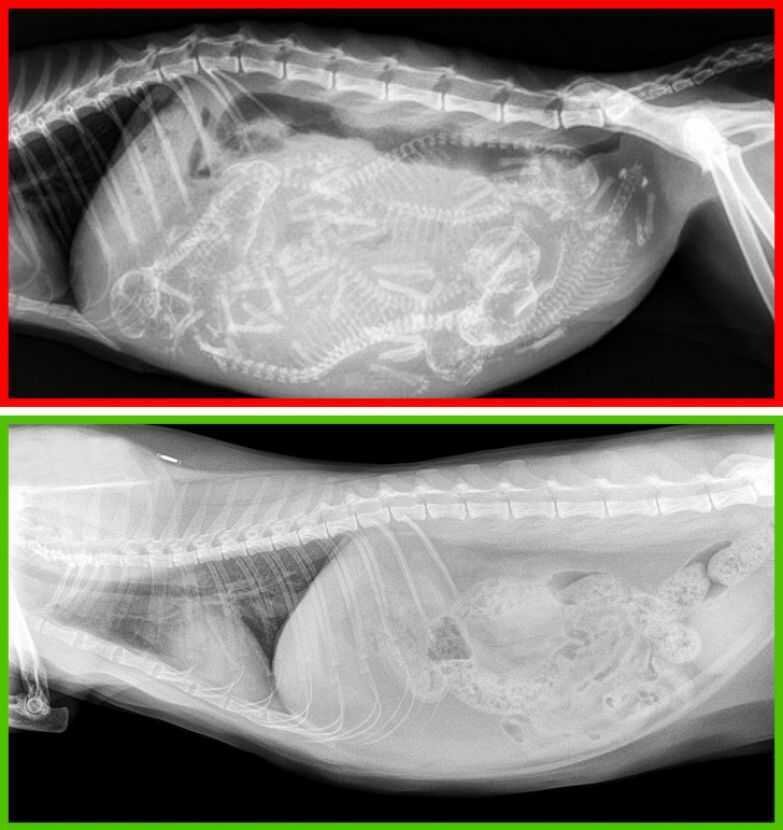

1. Отказываться от кастрации и стерилизации

Вверху — рентгеновский снимок беременной кошки, внизу — кастрированного кота.Эти процедуры в большинстве случаев положительно влияют на организм домашних животных. У кошек снижается риск возникновения рака молочной железы, а у котов — рака яичек. Кроме того, кастрированные коты реже убегают из дома и проявляют агрессию.